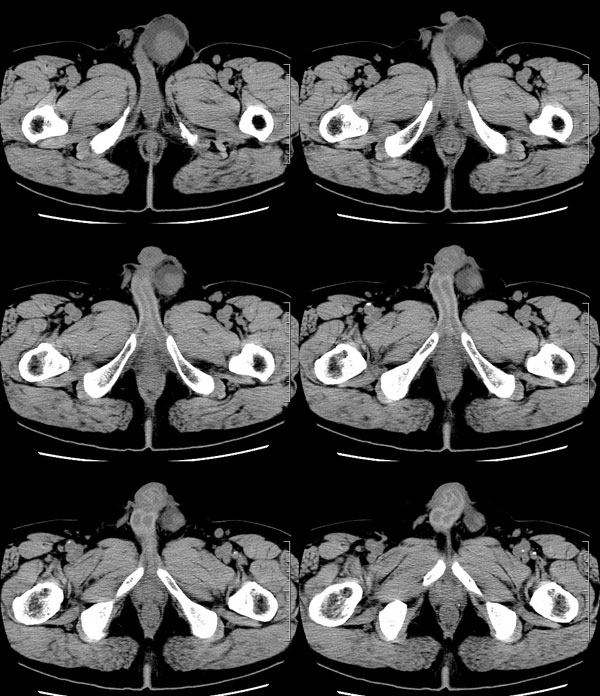

| 男性,69岁。自2个月前开始无意中发现左侧阴囊内一鸡蛋大小肿物,当时无伴疼痛等不适,未予重视。肿物逐渐增大,近段时间常伴左会阴部、腹股沟区牵扯不适,并于2周前在我院门诊行彩超检查提示“左侧附睾肿瘤可能,左侧睾丸鞘膜积液”。 专科检查:左侧阴囊肿大,其内可触及一鹅蛋大小肿物,表面光滑。肿物前部呈囊性感,后部质硬,按压无疼痛,无缩小,活动度良好。左侧睾丸未触及,透光试验(±)。                 王仕学发言:左侧睾丸见一密度不均肿块,边缘清楚,周围见水样密度影;考虑睾丸生殖细胞性肿瘤可能性大. 睾丸肿瘤占生殖系统肿瘤的3%-5%,占男性恶性肿瘤的0.5%-1.0%,其中生殖细胞性肿瘤占95%.睾丸肿瘤包括生殖细胞和非生殖细胞肿瘤两大类,前者占95%以上,后者不到5%.非生殖细胞肿瘤虽少见,但种类繁杂,主要有支持细胞、间质细胞和支持细胞-间质细胞瘤等功能性肿瘤,和间皮瘤、腺癌、横纹肌肉瘤、粘液性囊腺瘤、纤维上皮瘤、黑素神经外胚瘤、淋巴瘤等附属组织肿瘤。不同的病理类型的睾丸肿瘤发病率高峰不同,睾丸癌多发于35岁以前,精原细胞瘤发病高峰为30-35岁。精原细胞瘤约占睾丸肿瘤的60%,发病高峰在30-35岁。85%的患者睾丸有明显肿大,肿瘤局部侵犯力较低,肿瘤一般有明显界限。 手术:行“左侧附睾、睾丸、精索切除术”。 病理诊断:(左睾丸、附睾)肿物,为低分化腺癌。另送检(左精索远端)肿物,镜下亦为低分化腺癌。 免疫组化:ck(l)(++++)、cea(+++)、ca19-9(-)、psa(-)、plap(-)、p53(-)、vimentin(-)。 原贴地址:http://www.radinet.com.cn/forum_view.asp?forum_id=4&view_id=30707 |